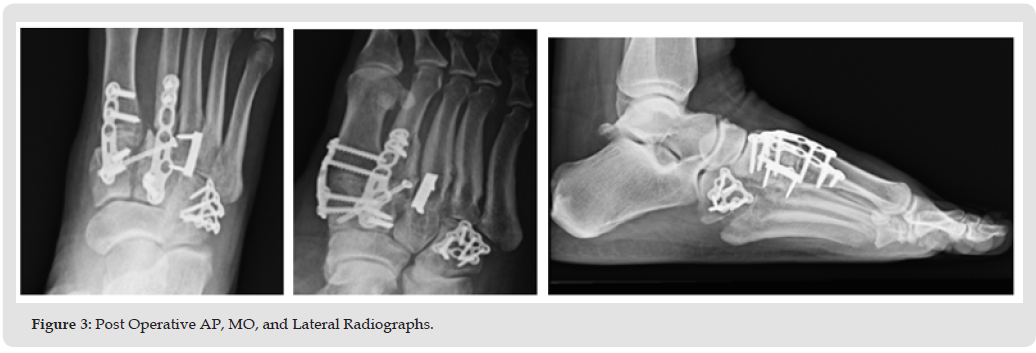

The patient is a 34-year-old morbidly obese female (height 65 in, weight 372 lbs., BMI-61) presenting with disabling right foot pain resulting from a fall (stumbling while stepping down off a porch), where she was taken to the ER and received pain medication which the patient claimed did not provide adequate relief. The surgeon saw her the following day, and X-rays showed a comminuted fracture of the second metatarsal base with intra-articular involvement and slight malalignment of the medial cuneiform with the first metatarsal base. There were also comminuted fractures involving the medial cuneiform, lateral cuneiform, and the cuboid bones, consistent with Lisfranc fracture. Other than morbid obesity, the patient history did not reveal any other significant co-morbidities. The risks and benefits of the surgery and length of recovery were discussed at length with the patient and the surgery was scheduled. The surgery consisted of TMT fusion of the first, second, and third TMTJ, and open reduction and internal fixation (ORIF) of the cuboid bone. At all times during the surgery particular care was used to avoid any damage to neurovascular structures. The first TMTJ was prepared by distraction and fenestration to allow for the placement of Catalyst Bone Graft substitute to promote fusion at the site and a Paragon 28 Lisfranc plate (Zimmer Biomet, Warsaw, IN) was inserted over the fusion site with both locking and non-locking screws.

The position and correct placement of the construct was confirmed using fluoroscopy. The second TMTJ joint was prepared using a separate incision however the second metatarsal base was in severe comminution and required a cannulated “home run” screw (provides axial compression across a joint) from the second metatarsal to the medial cuneiform. The medial and intermediate cuneiform surface was prepped for fusion and both Catalyst bone graft and a Paragon 28 Lisfranc plate were again used to secure the construct. The third TMTJ was similarly prepared with Catalyst used to promote fusion at the site. In this case a Paragon 15mm staple was used to complete the construct with adequate compression. The first and second TMTJ fusions were performed through separate incisions with the third using the same incision as the second. A separate incision was made for the ORIF of the cuboid bone where any hematoma or unwanted debris were cleared, the fracture was then reduced and held temporarily with a K-wire until a Paragon 28 cuboid fracture plate was placed on the dorsal aspect of the cuboid and accompanying screws were placed using standard lag technique. Intraoperative fluoroscopy showed adequate reduction and proper placement of all internal fixation. Both deep and subcutaneous wounds were closed, and the patient tolerated the procedure well. The procedure took approximately 3 hours with blood loss of only 100 ml.

After a brief period in PACU the patient was discharged from the hospital and returned home. The patient was followed closely post-operatively. Pain, swelling, and ROM continuously improved at each visit while the patient was NWB. At the two-month follow-up some early consolidation of the bone graft was observed at the TMTJ grafted sites as evidenced on X-ray, with no pain following ROM of the mid-tarsal joint. At this point, the patient was instructed to begin partial weight bearing with her boot and a walker. Narcotic pain medication was no longer needed by the patient and discontinued by 10 weeks. At 12 weeks a CT scan showed bony bridging at the arthrodesis sites along with appropriate reduction of the Lisfranc complex. At 14 weeks the patient had transitioned to weight bearing in a regular shoe and reports no pain on physical examination. From this point the patient will return for follow-up only if needed.

Early bone graft consolidation was noted in this patient as early as 8 weeks post-operatively and was complete as evidenced on CT scan by 12 weeks. The early graft consolidation in this case is both interesting and encouraging. This case sets the stage for further research with long term follow-up using Catalyst Bone Graft for any foot and ankle procedure where bone graft is required for predictable and rapid healing (Figures 1-5).